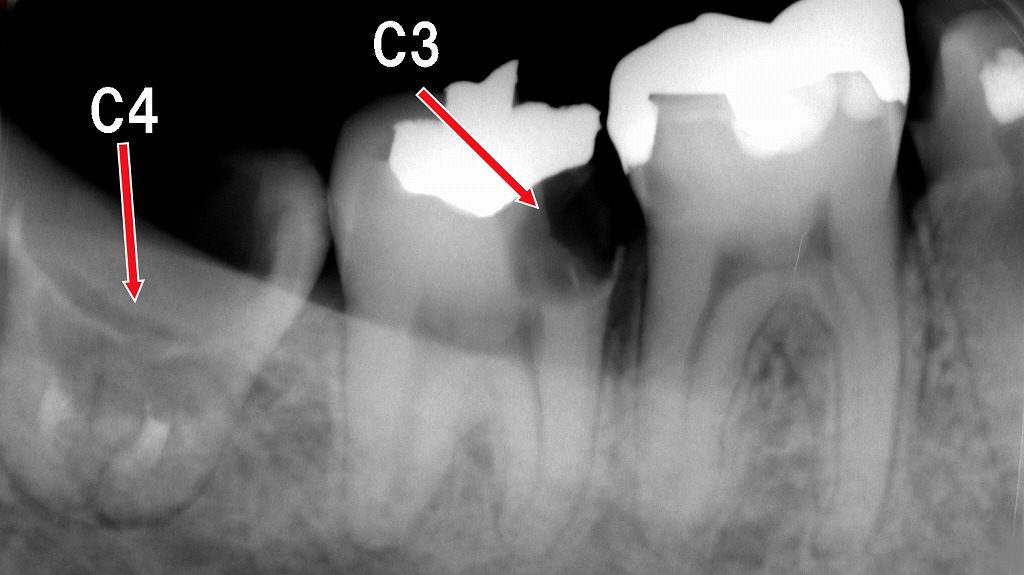

🦠 虫歯・神経の炎症との関係

歯の神経が炎症を起こすと、強い痛みの前段階として浮いたような違和感が出ます。

赤矢印(C3)は深い虫歯が神経まで達し、強い炎症(歯髄炎)を起こしている部位を示しています。歯髄炎になると、噛むと響く・歯が浮くような感覚・ズキズキした痛みが生じやすくなります。左側のC4は歯根まで進行した重度虫歯で、神経壊死や根尖病変の可能性が高く、放置するとさらに強い違和感や噛めない感覚の原因となります。